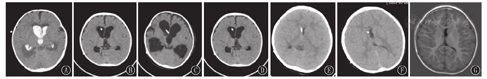

患儿均在急诊就诊期间行头颅CT检查,多数患儿急诊就诊时头痛剧烈难以耐受MRI,故仅个别患儿(例10)急诊完善头颅MRI检查。SVS发生时,头颅CT示脑室形态呈裂隙样、分流管位置贴壁。患儿脑室-腹腔分流术前、术后以及发生SVS时的头颅影像学表现见图1,图2。

本研究10例患儿诊断时头颅影像学均示脑室呈裂隙样,即SVS独特的影像学特征。通常脑脊液长期过度引流导致脑室缩小,急性静脉梗阻迅速进展时,脑室并不会扩大;若静脉窦压力高于分流泵压力时,分流泵开放、脑脊液引流,脑室进一步缩小,最终呈裂隙样脑室。可采用额枕角比率(FOHR)评估裂隙样脑室,即轴位侧脑室层面额角与枕角最大宽度的平均值/双顶径。FOHR正常值约为0.37,与年龄无关;FOHR≤0.2时,考虑裂隙样脑室[7]。值得注意的是,并非所有脑室呈裂隙样的患儿均为SVS,SVS诊断须具备相应临床症状。研究显示,分流术后超过50%的患儿可能会出现裂隙样脑室的征象,但仅6%~22%最终为SVS[15,16]。